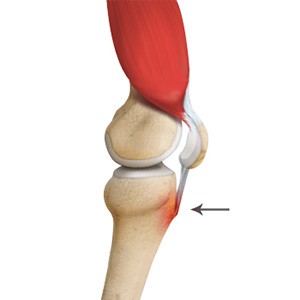

Patellar Tendinitis

Patellar tendinitis, also known as "jumper's knee", is an inflammation of the patellar tendon that connects your kneecap (patella) to your shinbone. This tendon helps in extension of the lower leg.